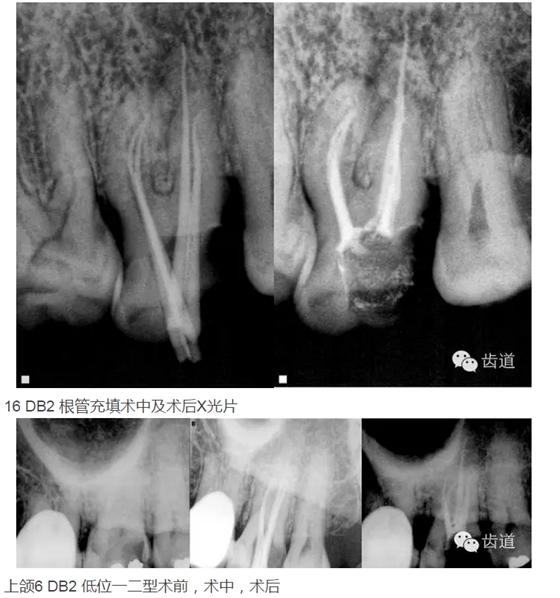

上頜第一磨牙:多為3-4個根管,MB2發(fā)生率約為60%;

上頜第二磨牙:與上頜第一磨牙相似,多為3根管,偶見雙鄂根管;